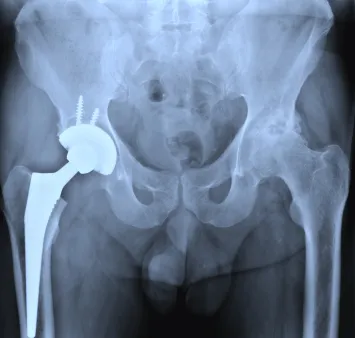

Zimmer manufacturers provide multiple types of hip implants hip replacement systems, including the Durom Cup. This Zimmer hip implant is a metal-on-metal hip implant designed to be used by patients who require hip replacement at a relatively young age. The Zimmer Durom Cup hip implant is designed to discourage the surrounding bone from growing in to the implant, and more than 13,000 people have received a Durom Cup hip implant in the United States.

The Zimmer hip implant was introduced in 2006, after it received approval by the Food and Drug Administration (FDA). In 2007, former Zimmer hip implant consultant, Dr. Lawrence Dorr, came out against the Zimmer metal hip implant, citing high failure rates. However, the company denied his opinions, saying that failure rates were caused by surgical error, not issues with the hip implant.

Patients continued to be implanted with Durom Cup hip implants, and complaints of failure rose from the field. In 2008, the company briefly suspended sales of the product, and consumers wondered if the Durom Cup implant was going to be recalled. However, a month afterward the company started selling the Zimmer hip implants again, saying that it had found no evidence that the Zimmer hip implants were defective in their design.

Consumers disagreed. They said that the metal-on-metal design didn’t hold together well enough and that the Zimmer hip implants loosened and failed over time. These patient opinions were backed up by a University of Wisconsin study that showed that Durom Cup implants had a higher failure rate statistically than other types of hip implants.